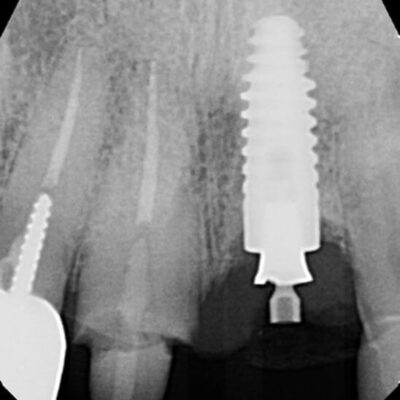

The patient presented on referral from Dr. S. for evaluation and implant mechanical rescue (IMR) to retrieve a fractured zirconia abutment from the 4.5×14 Ankylos CX implant in the #9 site. This fracture occurred secondary to a traumatic accident while using an exercise band failure as the patient was working out. The traumatic impact not only fractured the zirconia abutment on #9 but the #8 tooth as well. After having #8 stabilized with endodontic treatment, Dr. S. placed a post core and provisional.

As the implant was placed by Dr. K. about 8 years ago, he was referred there for recovery of the fractured zirconia abutment and abutment screw. Recovery of fractured zirconia abutments from Ankylos implants are almost always difficult and tricky due to the tight conical connection at 5.7 degrees and the hardness of the zirconia. Because the abutment screw is free floating (the through bore is smaller than the threads), this presents an additional roadblock to recovery. Evidently, the patient was seen for about 1.5 hours, and while not excessive in my experience, there was only partial recovery of the fractured components. On examination, it was clear while some of the conical portion of the zirconia abutment had been removed, so had some of the implant top. The decision was made to proceed with finishing the recovery as I felt the remaining portion of the conical connection was enough to provide a stable abutment to implant connection. As the area had been flapped the previous day the proximal sutures were left intact and only a small amount of tissue contouring was needed to provide adequate access to visualize the implant top. The site was photographed prior to proceeding with further recovery efforts. As the screw head had already been removed along with the top two thirds of the conical abutment, the bottom portion of the conical abutment was concentrically removed with a surgical length high speed round diamond under microscope visualization. This was done to the level of the indexing splines which start approximately 3mm below the top of the implant. At that time, the zirconia splines became visible, and several small chunks of zirconia were retrieved. With careful manipulation of the screw fragment with an endodontic explorer and modified endodontic spoon, the screw was mobilized and maneuvered so a surgical length ¼ round bur could be placed on the screw outside diameter (OD), in an open implant spline. Again, with microscope guidance, the screw fragment was recovered along with the remaining zirconia fragments. The implant was cleaned, and the supplied healing abutment was placed finger tight. The recovery was completed without further damage to the implant. The patient’s existing provisional was modified to fit the healing abutment contours and was recemented with Tempbond clear, as it appeared to be the cement that was previously used. The patient was dismissed to return to Dr. S. for continuation of his restorative treatment plan.

Due to the initial recovery effort, without a doubt, the implant top was altered and some of the conical connection was lost. I would think a custom titanium abutment would be preferable to zirconia. This abutment connection is small to begin with, 3.97sq mm at the implant top, and a strong argument can be made to avoid zirconia altogether in most if not all Ankylos applications. With the loss of approximately .5-.6mm of conical connection height this connection will become even smaller, and more prone to fracture. As stated earlier, I believe the stability of the abutment to implant connection will be stable in regard to abutment and screw stability, but that is due to the 5.7-degree conical interface and its ability to protect the screw. Use of a stronger abutment material that is more resistant to torsional loads might compensate for the decrease in surface area size. Caution should be taken to avoid non-OEM abutment components as several have larger through bore designs to avoid the laser assembled free floating screw design which will decrease the abutment strength even further. C.A.M.